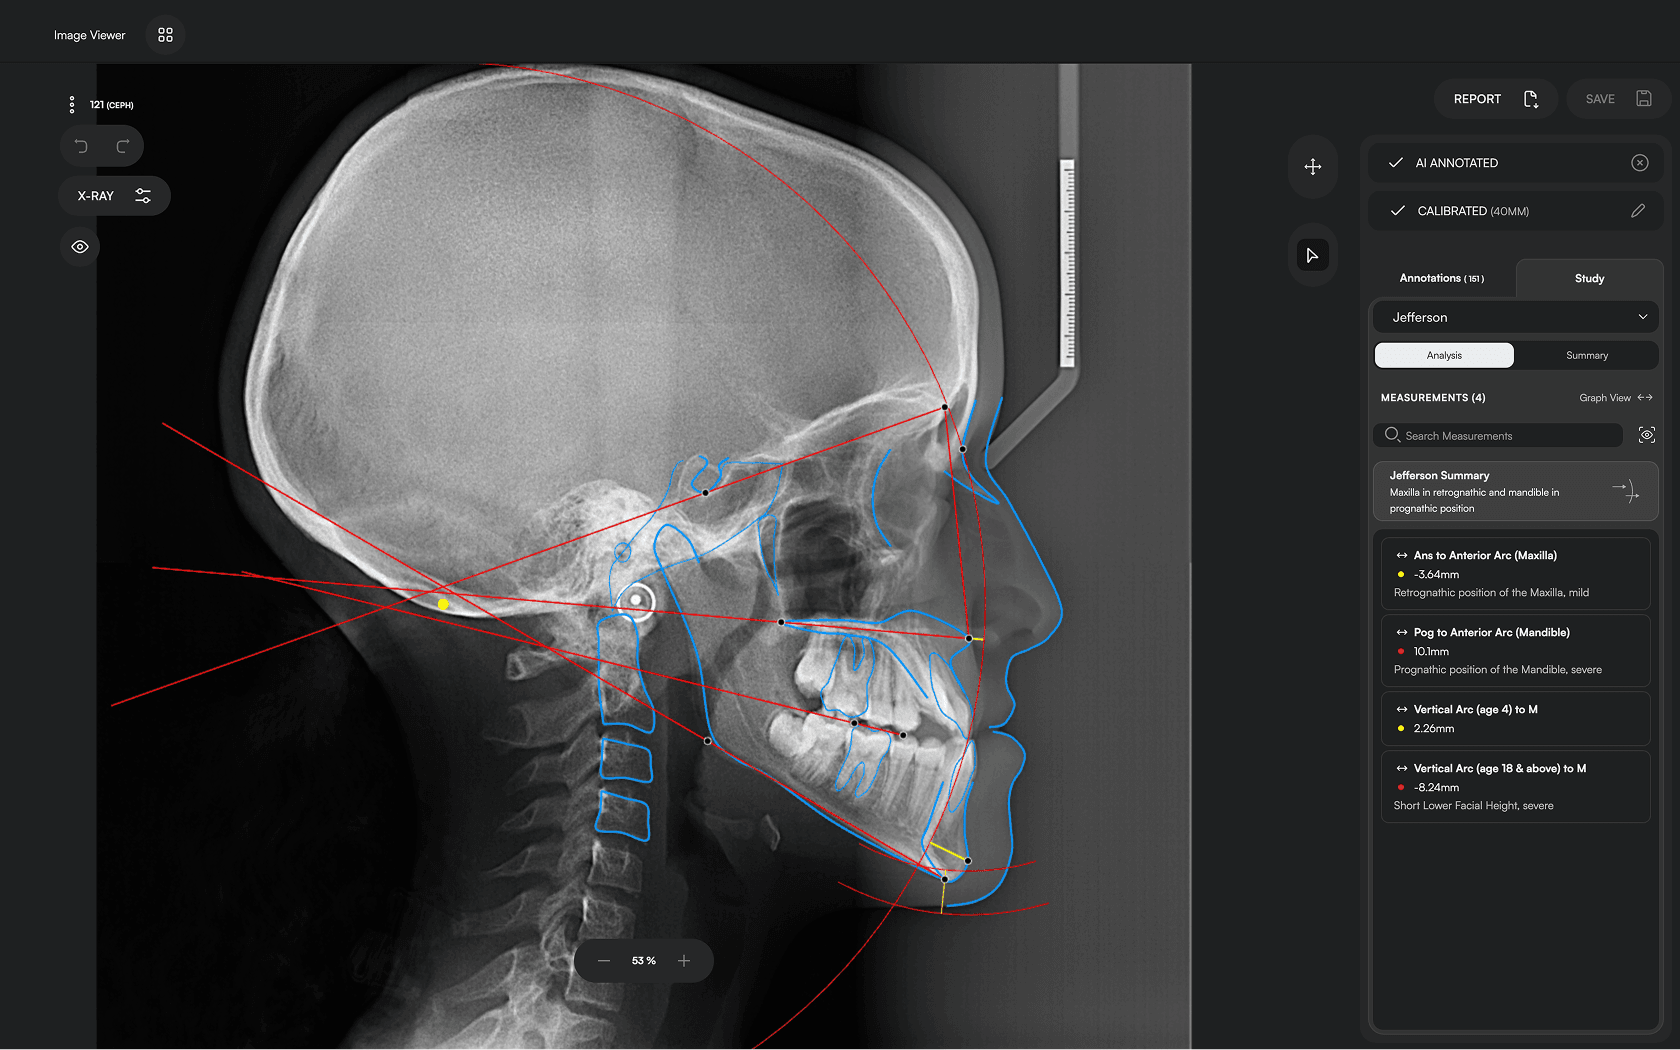

Diverse Analysis

Access automated studies like Steiner and Jefferson to assist in clinical assessment and enhance case evaluations.

Powerful Insights

Experience a comprehensive assessment of skeletal, dental, and soft tissue discrepancies.